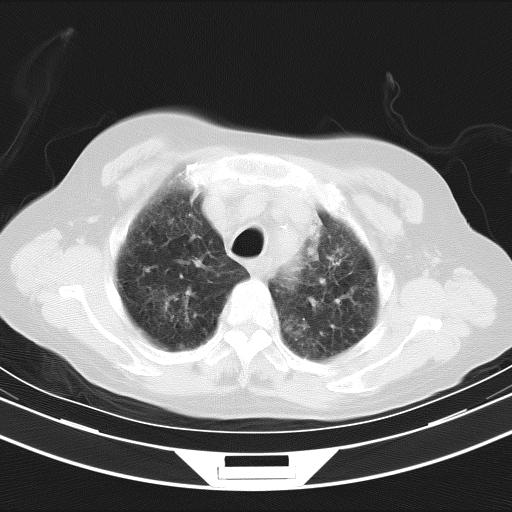

老年女性,嗜睡3天,意识模糊。轻咳,无发热。

双肺多发淡片影,毛玻璃影,,支持支气管肺炎,,建议血气找原因,,嗜睡是否肺性脑病?有没有慢支病史?

1)两肺感染性病变;建议抗炎治疗后复查。2)纵隔淋巴结肿大。3)左侧胸腔积液。

1)先考虑两肺感染性病变;建议抗炎治疗后复查。

2)纵隔淋巴结肿大。

3)左侧胸腔积液。